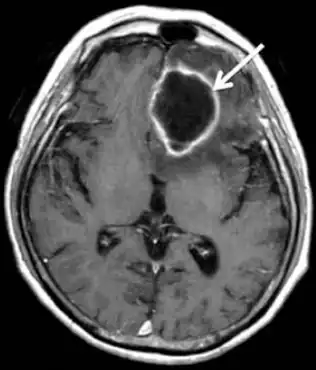

MRI of brain revealed a mass in left frontal lobe that was ring-enhanced

Early and massive tissue necrosis is a specific feature of C. koseri brain infection. The early stage of the disease predominates in the white matter, causing cerebritis; the later stage is marked with necrotic cavities in multiple locations. The cavities are initially square in shape and not tense, but when pus forms and collects in these cavities, they tend to become more rounded in shape; a persisting cavity leads to septated ventriculitis that may result in multicyctic hydrocephalus.[3]

Early, cerebritis is seen, and multiple large cavities can be seen in the late stage of the disease; abscesses formation, contraction of the cavities, and hydrocephalus due to ventriculitis are observed in the late follow up.[3][6]

The differential diagnosis of C. koseri brain abscesses can be confused with other related diseases, so diagnostic imaging is important to confirm this bacterium. The significant feature of C. koseri is the necrotic cavity which cannot be misidentified as earlier ischemic or hemorrhagic insult or other mass lesions; congential/neonatal tumors are uncommon (choroid plexus papillomas, craniopharyngiomas, teratomas); even when they present, they are different from the inflammatory ring of a cerebral infection. Early cerebritis should not be mistaken for normal, immature white matter, nor for cicatricial leukomalacia.[3][6]